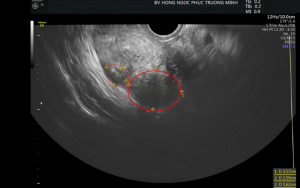

Khám phụ khoa & siêu âm: Đánh giá tử cung, buồng trứng và loại trừ các bệnh lý phụ khoa.